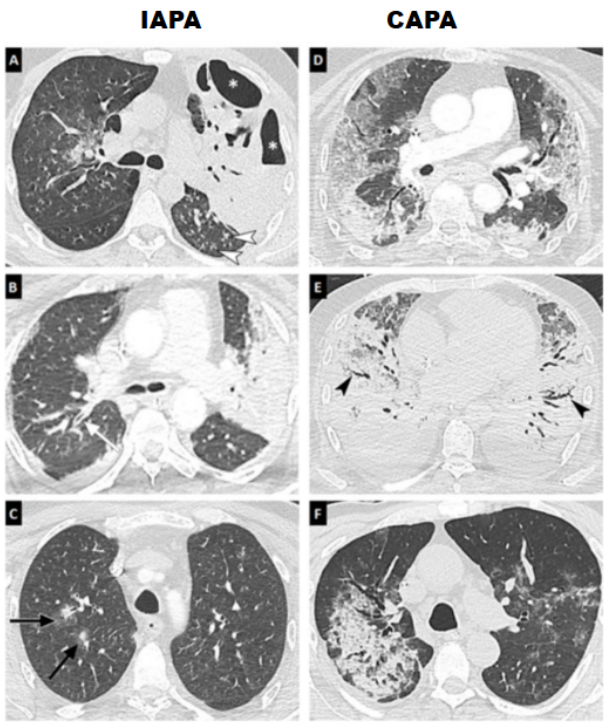

IA的诊断需要正确的标本、正确的检查技术和正确的检查结果。2020年EORTC和MSGERC发布的《侵袭性真菌病的共识定义的修订和更新》中提出的IA的确诊标准:①无菌标本微生物分析:针吸或活检获得标本,进行组织病理学、细胞病理学或直接显微镜检示:菌丝或黑酵母样形态,同时伴随组织损伤证据。②无菌标本培养:从临床或影像学显示的病灶部位(正常无菌部位),通过无菌操作位获取标本,示透明或着色的霉菌。③血标本:同时存在感染的过程中,血培养示霉菌。④组织核酸诊断:福尔马林固定石蜡包埋组织中发现霉菌时,PCR和DNA测序检测到真菌DNA。IA的临床诊断—宿主因素及临床标准:患者需符合1项宿主因素、1项临床标准和1项微生物学标准:(1)宿主因素:①近期发生中性粒细胞缺乏(中性粒细胞计数<0.5×109/L)并持续超过10天;②接受异基因造血干细胞移植;③既往60天内,长时间使用皮质类固醇(除外变应性支气管肺曲霉病):超过3周的平均最低剂量为0.3 mg/(kg·d)的强的松当量;④既往90天内接受T细胞免疫抑制剂治疗,如:环孢素、TNF-α阻滞剂、特定的单克隆抗体(如阿仑单抗),或核苷类似物;⑤遗传性严重免疫缺陷(如慢性肉芽肿、STAT3缺陷或严重联合免疫缺陷);⑥血液恶性肿瘤患者;⑦实体器官移植受者;⑧接受B细胞免疫抑制剂治疗, 如布鲁顿酪氨酸激酶抑制剂(如:依鲁替尼);⑨累及肠、肺或肝的Ⅲ级或Ⅳ级GVHD, 且对一线皮质类固醇治疗无效。(2)临床标准:①肺曲霉病—存在以下4种CT特征中的一种:a. 边界清楚的致密病变,伴或不伴晕征;b. 空气新月征;c. 空洞;d. 楔形和节段性或大叶性实变。②气管支气管炎:镜下可见气管支气管黏膜溃疡,结节,伪膜,斑块,或焦痂。③鼻窦感染:a. 急性局部疼痛(包括放射至眼部的疼痛);b. 鼻溃疡伴黑痂;c. 从鼻窦延伸至穿过骨屏障,包括进入眼眶。④中枢神经系统感染—存在以下2种症状中的1种:影像学局灶性病变;MRI或CT提示脑膜强化。IAPA和CAPA疾病定义、区别COVID-19患者细支气管炎性和肺炎型的诊断标准见表1。表1 IAPA和CAPA疾病定义、区别COVID-19患者细支气管炎性和肺炎型的诊断标准IAPA和CAPA疾病定义专家共识指出,在IAPA和CAPA早期通常表现为非典型影像,如:外周、双侧磨玻璃影±实变或小叶内条索影(碎石征);多发圆形磨玻璃影±实变或小叶内条索影(碎石征);曲霉细支气管炎表现为外周细支气管炎浸润。CAPA共识同时指出:多发肺结节或空洞(单纯的COVID-19感染少见),当出现此类表现应推进进一步的IPA诊断。图10为3例IAPA和3例CAPA患者的肺部影像学表现。A~C为IAPA患者影像学,单侧或双侧实变区伴有空气支气管征(A、B)、空洞形成(*)、树芽征(白色箭头)、支气管壁增厚(白色箭头),或偶见结节伴晕轮征(C,黑色箭头);D~F为CAPA患者影像学,双侧区域磨玻璃影和/或广泛的碎石征(D)、与外周牵拉性支气管扩张相关的广泛实变(E,黑色箭头),或相对少见的单侧区域实变(F)。图源:J Fungi (Basel), 2021, 7(5):388.CAPA影像学形态多变,呈气道分布、具有多病灶、多形性、多变性的特征。可能是一些多发空洞样多形性改变(图11)。IM的确诊标准与前文所述IA的确诊标准相同。其临床诊断需符合1项宿主因素、1项临床标准和1项微生物学标准。粒细胞缺乏、铁载量增加、糖尿病、血液恶性肿瘤、器官移植、造血干细胞移植、静脉药物滥用、使用激素、使用伏立康唑、使用广谱抗细菌药物、肾功能不全、创伤及烧伤都是毛霉病的危险因素。不同毛霉病患者出现不同的临床表现,主要取决于宿主的免疫状态、感染程度和受累器官。毛霉病最常表现为鼻-眶-脑感染,通常发生于真菌孢子吸入鼻窦;这种情况下,感染可能停留在局部,症状与急性鼻窦炎类似:伴发热、头痛、鼻窦疼痛和鼻塞。毛霉病也可表现为吸入孢子后肺部感染,常见发热、胸痛、呼吸困难和咯血(可能是大量和致命的),咯血主要是由于菌丝侵犯血管和继发出血。对于免疫功能低下患者,毛霉感染可能侵犯眼眶和上颚,并进一步延伸到大脑;局部组织侵犯可导致显著的临床异常,包括视力丧失、颅神经麻痹和精神状态改变。皮肤毛霉病患者多数无明显的免疫抑制,但既往有严重创伤;感染可局限于局部或扩展到更深组织,包括周围的骨骼、肌肉和肌腱;病变开始时出现疼痛性红斑和硬化,并逐渐发展为坏死,通常进展为坏死性筋膜炎。在COVID-19患者中,毛霉主要影响眼睛、口腔和大脑,常表现为:眼部干性坏疽,眶鼻区、上颚或口腔底的压疮等。“反晕轮征”是毛霉病的一种特异性征象。既往多项研究及病例报道提示:针对免疫功能不全患者,反晕轮征内的网状结构和较厚的外缘强烈提示患者可能为毛霉病。研究显示,19%~94%的肺毛霉病患者的影像学表现为反晕轮征,且反晕轮征在粒缺患者中更为常见;此外,毛霉病的连续胸片检查显示出快速进展(图12)。图12 一例41岁因急性髓系白血病接受干细胞移植的女性患者肺毛霉病快速进展图源:Radiographics, 2020, 40(3):656-666.鼻-眶-脑是COVID-19继发IM的主要类型(74%),糖尿病基础疾病和酮症酸中毒在其中扮演重要角色。图13描述了COVID-19患者吸入毛霉孢子(a)并在鼻腔内定植(b),在代谢异常条件下生成菌丝(c),毛霉侵入骨骼并延伸至蝶窦进入颅内(d)或经由上颌窦和筛窦可导致眼眶受累(e)。图源:Br J Radiol, 2021, 94(1127):20210648.侵袭性真菌病(IFD)的诊断分为确诊、临床诊断、拟诊和未确定四个级别(表2)。这也决定了侵袭性真菌病的起始治疗方案,经验性治疗要避免病情加重。注:IFD为侵袭性真菌病;G为(1,3)-β-D葡聚糖;GM为半乳甘露聚糖;“/”表示不需要;确诊IFD不依赖患者宿主因素、临床和影像学表现评估。肺部真菌感染存在诊断难和治疗难的特点。诊断方面:①直接镜检+培养的阳性率较低,一次性取材也影响阳性率;②组织病理学检查、抗原抗体检测:GM/G试验需要多次检测来降低假阳性率、受β-内酰胺类抗菌药物影响;③影像学:早期缺乏特异性。治疗方面:①治疗药物有限:目前仅有多烯类、唑类、棘白菌素类;②药物药代动力学:受食物、pH影响;需检测血药浓度;③药物不良反应:包括肝肾功能损害、神经毒性、视觉障碍、输液反应等;④药物配伍禁忌:泊沙康唑、伏立康唑禁止与拮抗药物(利福平)、卡马西平、CYP3A4底物联用等。